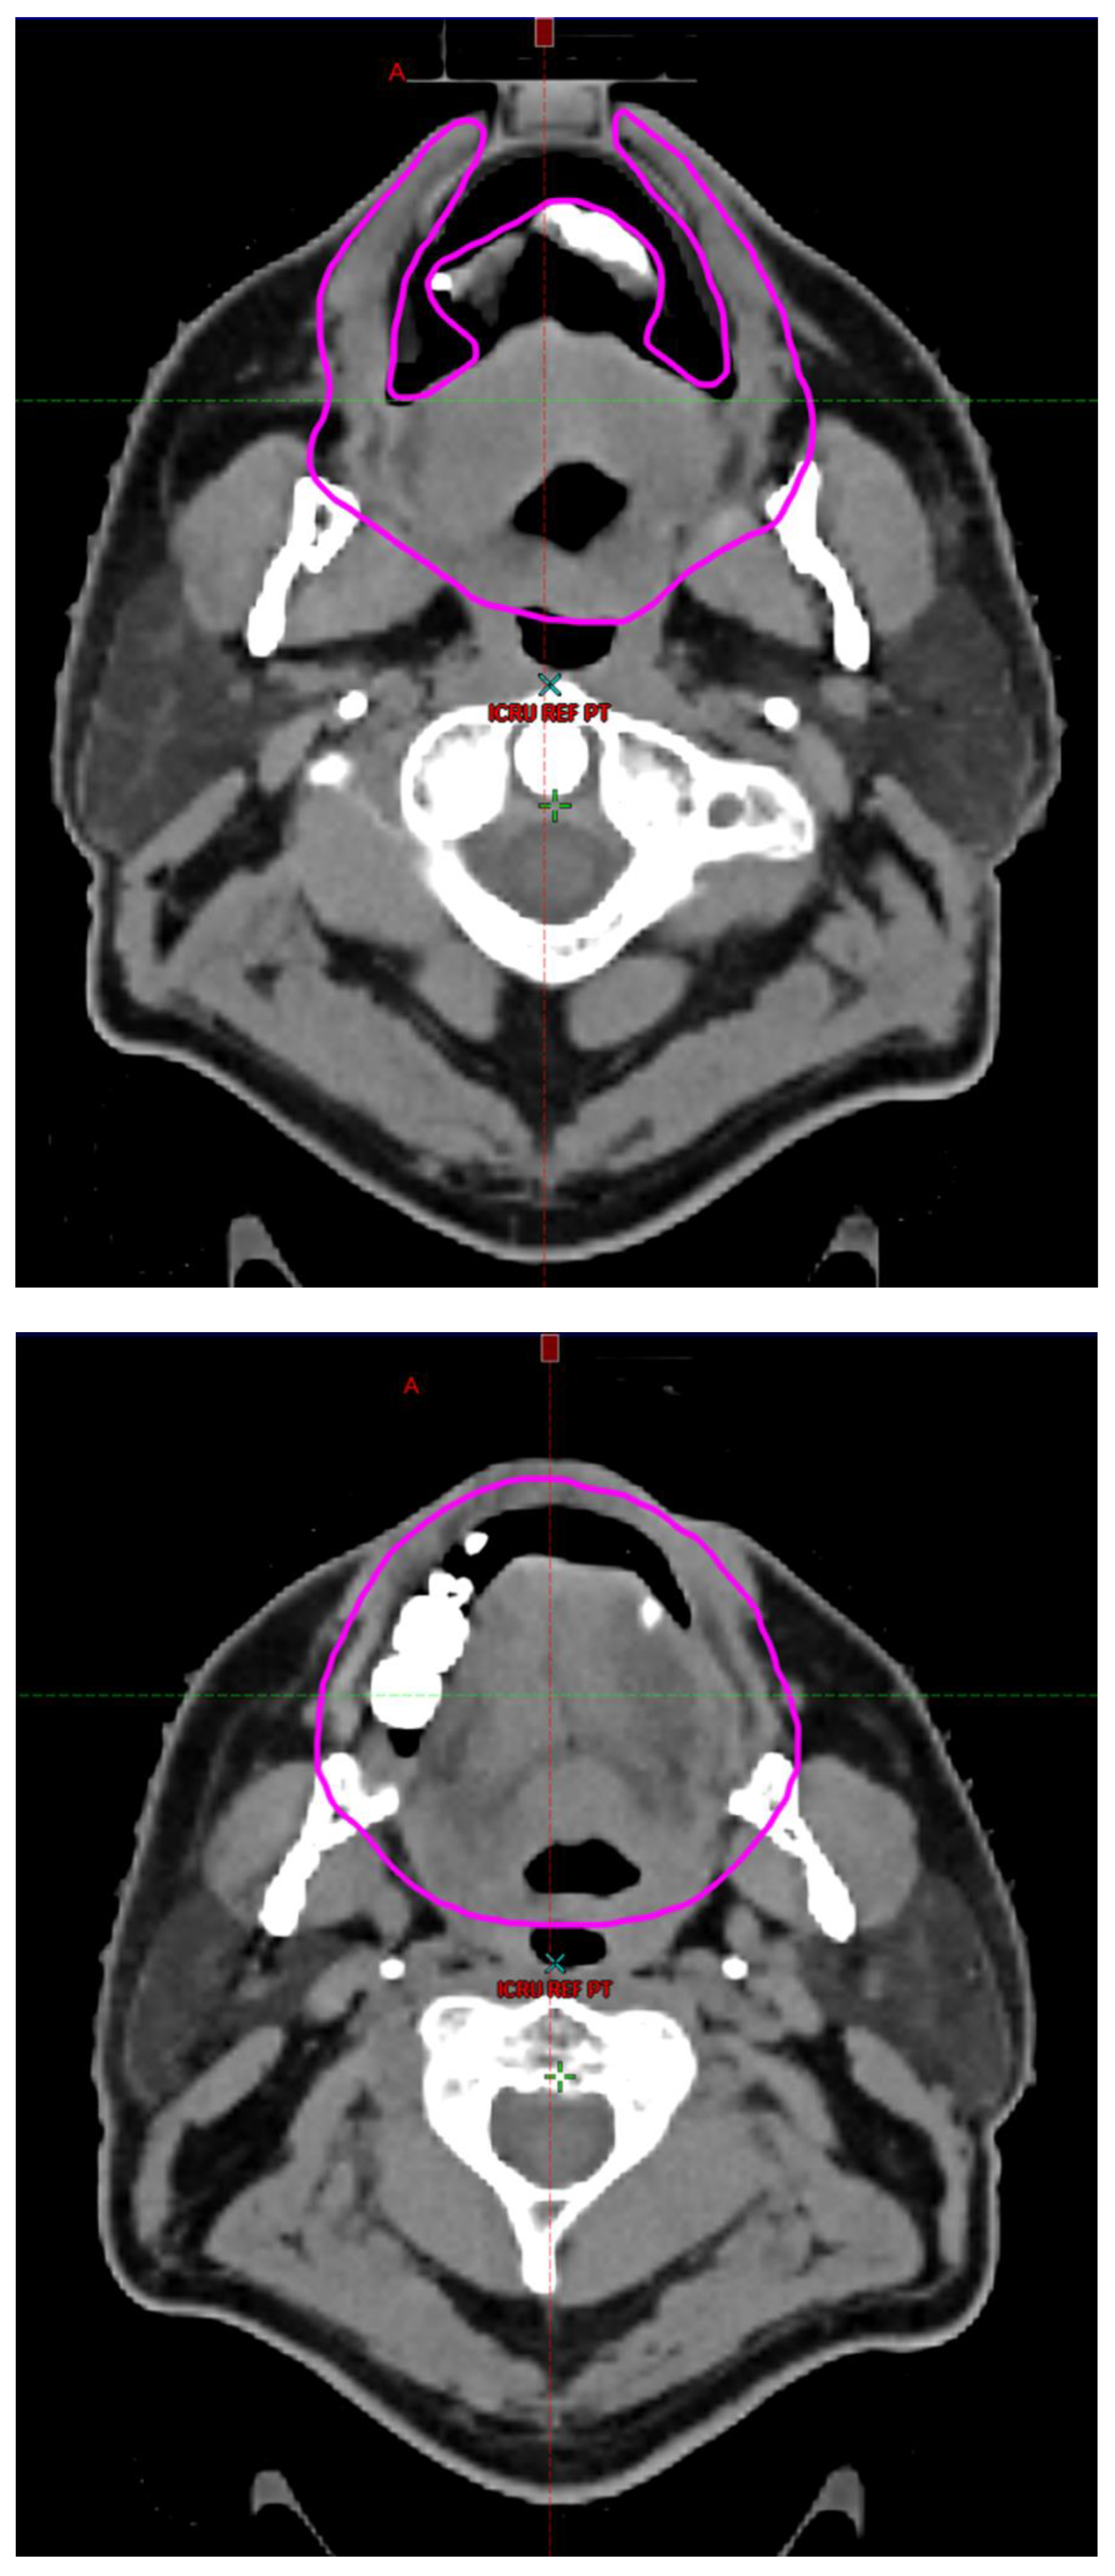

Radiotherapy treatment plans were created, and dose volume histograms (DVH) were generated using the Eclipse treatment planning system (Varian Medical Systems, Palo Alto, CA). The standard photon treatment plans consisted of three volumetric modulated arc therapy fields. The standard proton treatment plans consisted of three to four fields with the pencil beam scanning technique. For proton therapy plans, the RT dose was scaled by 1.1 to account for the difference in relative biological effect when compared to conventional photon treatments. A definition for oral cavity OAR avoidance structure evolved at our institution between 2003 and 2016 when it was formalized and accepted as the consensus standard for treatment planning (Figure 2). The DVH statistics for the oral cavity OAR, and the mean dose to the left and right submandibular glands, left and right parotid glands and total parotid glands were calculated and extracted. Pharyngeal constrictor, intrinsic and extrinsic muscles of the tongue, and laryngeal DVH statistics were not included since swallowing function is not a primary endpoint for this study. There were four patients who did not complete the planned course of treatment. In these cases, the prescribed dose was scaled to the delivered dose.

The superior extent of the oral cavity OAR avoidance structure includes all the mucosa of the hard palate. The contouring of the OAR begins superiorly at the first sign of mucosa on the alveolar ridge of the maxilla (medial and lateral) and hard palate. It then continues inferiorly to include the mucosa of the upper and lower lip, mucosa of the hard and soft palate including the uvula, the buccal mucosa including the buccinator muscles, the mucosa of the retromolar trigone, the entire tongue (anterior two-thirds, dorsal surface and tongue base), floor of mouth, sublingual glands, gingival mucosa of the mandible (lingual and buccal surfaces), and ending at the level of the cranial edge of the hyoid bone and caudal edge of the mandible. It also includes the maxillary and mandibular teeth if present. The posterior extent includes the soft palate, uvula, and tongue base. The anterior extent includes the mucosal surface of the posterior one-half of the lips and the gingival mucosa of the maxillary and mandibular alveolar ridges and retromolar trigone. The lateral extent includes the buccal mucosa and buccinator muscles. The oral cavity OAR contains most of the taste buds which are located within the mucosa of the anterior two-thirds of the tongue, the floor of mouth, the buccal mucosa, the lips, the pharynx (including the soft palate, uvula, and base of tongue), the larynx (epiglottis) and upper third of the esophagus [4]. The oral cavity OAR also contains the minor salivary glands located within buccal, labial, lingual, soft palate, lateral parts of the hard palate, and floor of the mouth submucosa and in the trough circling the circumvallate papillae on the dorsal surface of the tongue near the terminal sulcus [3]. Therefore, the oral cavity OAR for radiotherapy (RT) treatment planning purposes is defined as including the anterior two-thirds of the tongue, floor of mouth, buccal mucosa, mucosal surface of the lips, soft palate, uvula, base of tongue, hard palate and circumvallate papillae on the dorsal surface of the tongue. The gingival mucosa of the alveolar ridges of the mandible and maxilla and the mucosa of the retromolar trigone are also included in the definition to further reduce the incidence and severity of painful oral mucositis. Finally, the sublingual glands are included in the oral cavity OAR structure. The larynx (epiglottis) and upper third of the esophagus are not included in this OAR volume because they are included in their own OAR avoidance structure (larynx, cricopharyngeal inlet, cervical esophagus).

Figure 2. Oral Cavity Organ at Risk (OAR) Avoidance Structure Definition.

Preprints 93045 g002aPreprints 93045 g002bPreprints 93045 g002cPreprints 93045 g002d